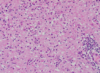

Name the pathologic process.

Name & describe the predominant cell type.

What are these cells typically seen with?

Astrocytosis

Alzheimer’s type II astrocytes: enlarged, vesicular nuclei

Typical of hepatic encephalopathy